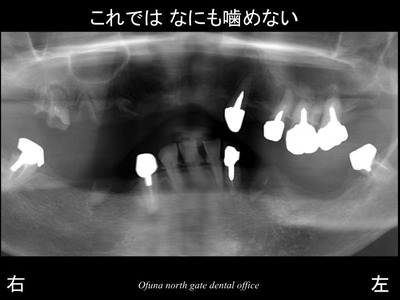

以下が初診時のレントゲン写真です。

多くの歯が欠損しているのが分かるかと思います。

被せ物が次々に取れていき、抜歯を繰り返しており、

噛む場所がなくなってしまったとのことで紹介を受けて来院された方です。